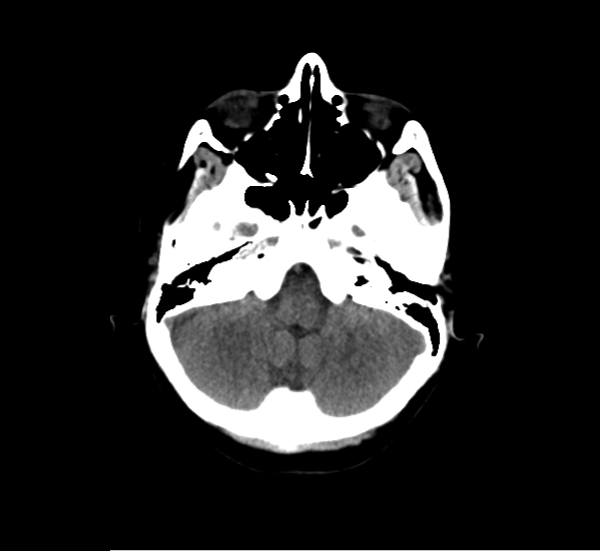

CT Brain Anatomy